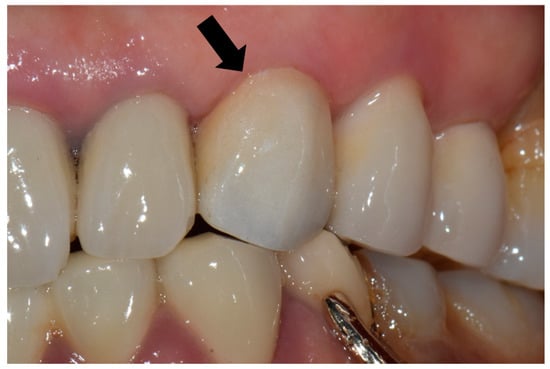

For each case, the master cast was fabricated with type III dental stone (Snow rock dental stone, DK Mungyo, Gimhae, Korea) and digitally scanned using a model scanner (3Shape D2000, 3Shape, Copenhagen, Denmark). All restorations were designed by dental technicians with 15 years’ experience, using the CAD software (3Shape CAD Design software, 3Shape, Copenhagen, Denmark) following the manufacturer’s instructions. The anatomically contoured zirconia crowns were milled (Cori TEC one, imes-icore, Eiterfeld, Germany) from fully-sintered (Y, Nb)-TZP blocks (Perfit-FS, Vatech MCIS, Gyeonggi-do, South Korea). For optimal shade reproduction, the milled restorations were treated with the zirconia-coloring liquid at 780 °C for 1 min with a firing rate of 45 °C/min using a sintering furnace (Austromat D4, Dekema, Freilassing, Germany). At the third visit, the definitive restoration was carefully evaluated on each participant’s abutment regarding the shape, adaptation, color match, proximal contact, and occlusion (Figure 1). If adjustments were needed, it was conducted using a fine-grained diamond bur with a high-speed handpiece. Resin-modified glass ionomer cement (GC FujiCEM 2, GC, IL, USA) was used to cement the crown in place. The participants were instructed to revisit the clinic for follow-up, as scheduled.

Figure 1. Fully sintered (Y, Nb)-TZP (tetragonal zirconia polycrystal) crown was placed on the maxillary left canine (black arrow).